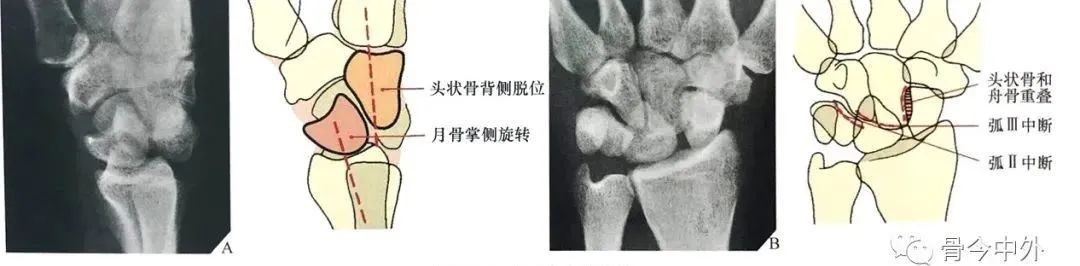

在腕关节侧位片上,一旦头状骨长轴骨偏离月骨和桡骨远端表面所形成的直线而向背侧成角或掌侧成角,即可诊断月骨周围脱位。

月骨周围脱位时虽然月骨半脱位造成一定程度的月骨倾斜角,但月骨仍保留在与桡骨远端表面所形成的关节内(图24A)。

在背掌位片上,腕骨的近侧列和远侧列重叠、弧线 II 和弧线 Ⅲ 在头状骨的位置中断,提示月骨周围脱位(图24B)。

图24 月骨周围脱位。(A)腕关节侧位X线片显示典型的相对于月骨的头状骨背侧移位,虽然月骨轻度掌侧旋转,但仍保留在与桡骨远端所形成的关节内。注意第三掌骨、头状骨与月骨和桡骨远端所形成的直线中断。在背掌位投照X线片上(B),月骨周围脱位表现为由弧 II 和弧 Ⅲ 的中断所造成的腕骨近侧列与远侧列的重叠。